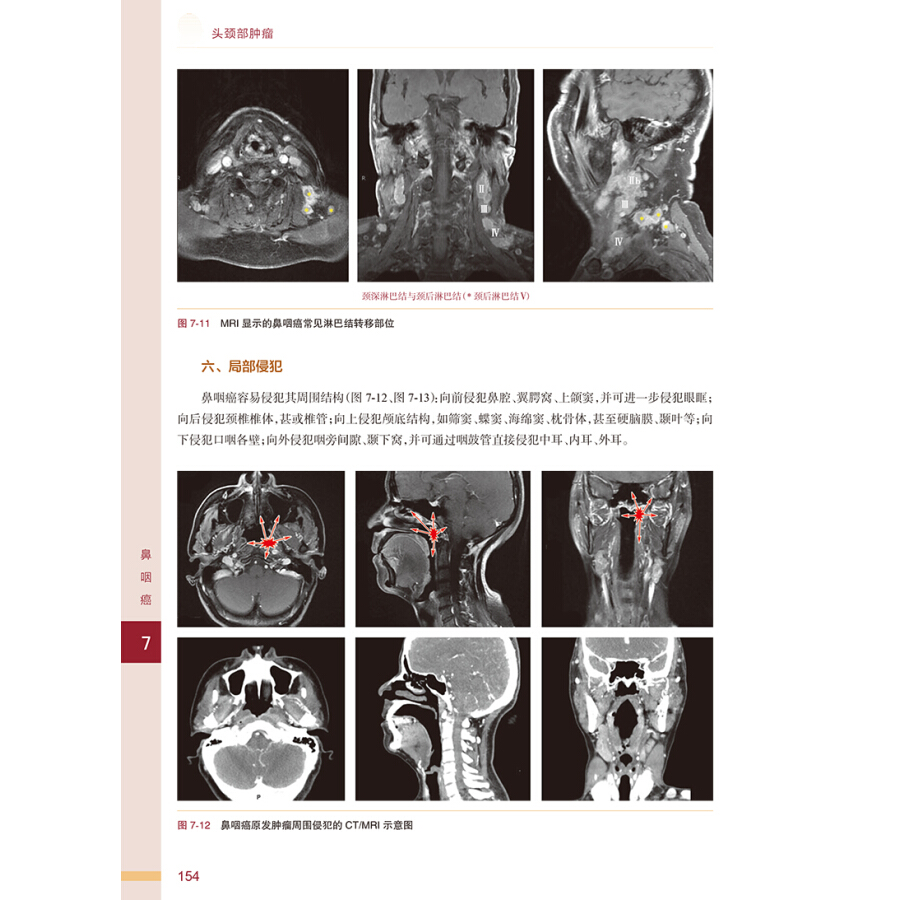

第七章 鼻咽癌 / 148

第一节 应用解剖 / 149